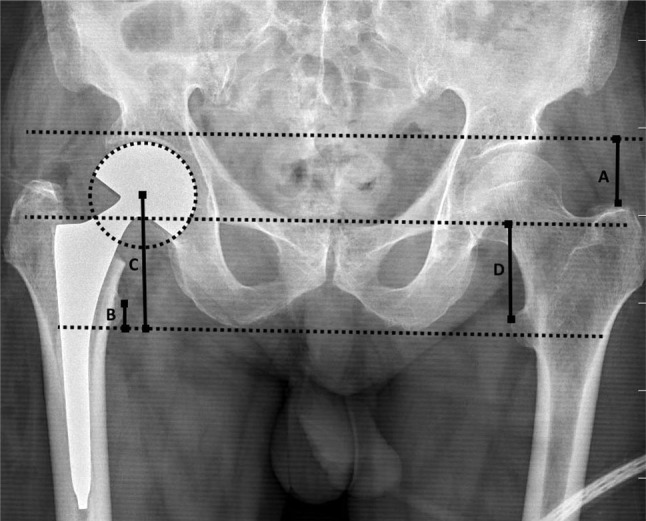

Patients and methods: Between January 2017 and January 2022, a total of 97 patients (39 males, 58 females; mean age: 77.8±7.1 years; range, 61 to 91 years) who underwent pelvic radiographic evaluation and hemiarthroplasty (HA) due to femoral neck fracture were retrospectively analyzed. For ATD measurement, the distance between the line connecting the upper cartilage of the acetabulum (AC) and the extreme point of the greater trochanter (GT) was used. The AC-GT measurement on both sides was compared with bottom of the ischial tuberosities-lesser trochanter (BI-LT), center of the femoral head-BI (CH-BI), inferior acetabular teardrops-LT (IT-LT) measurements. The agreement between the methods was examined with the intraclass correlation coefficient (CCI).

Results: According to the AC-GT & BI-LT, AC-GT & BI-CH methods, there were very strong (ICC: 0.75), moderate (ICC: 0.69) and acceptable (ICC: 0.33) agreements, respectively. Significant agreement was found between all measurements (p<0.001). A positive correlation was detected in the correlation analysis of all measurements (p<0.001). Intra- and interobserver agreement for ATD measurement (AC-GT) was excellent (ICC: >0.8).